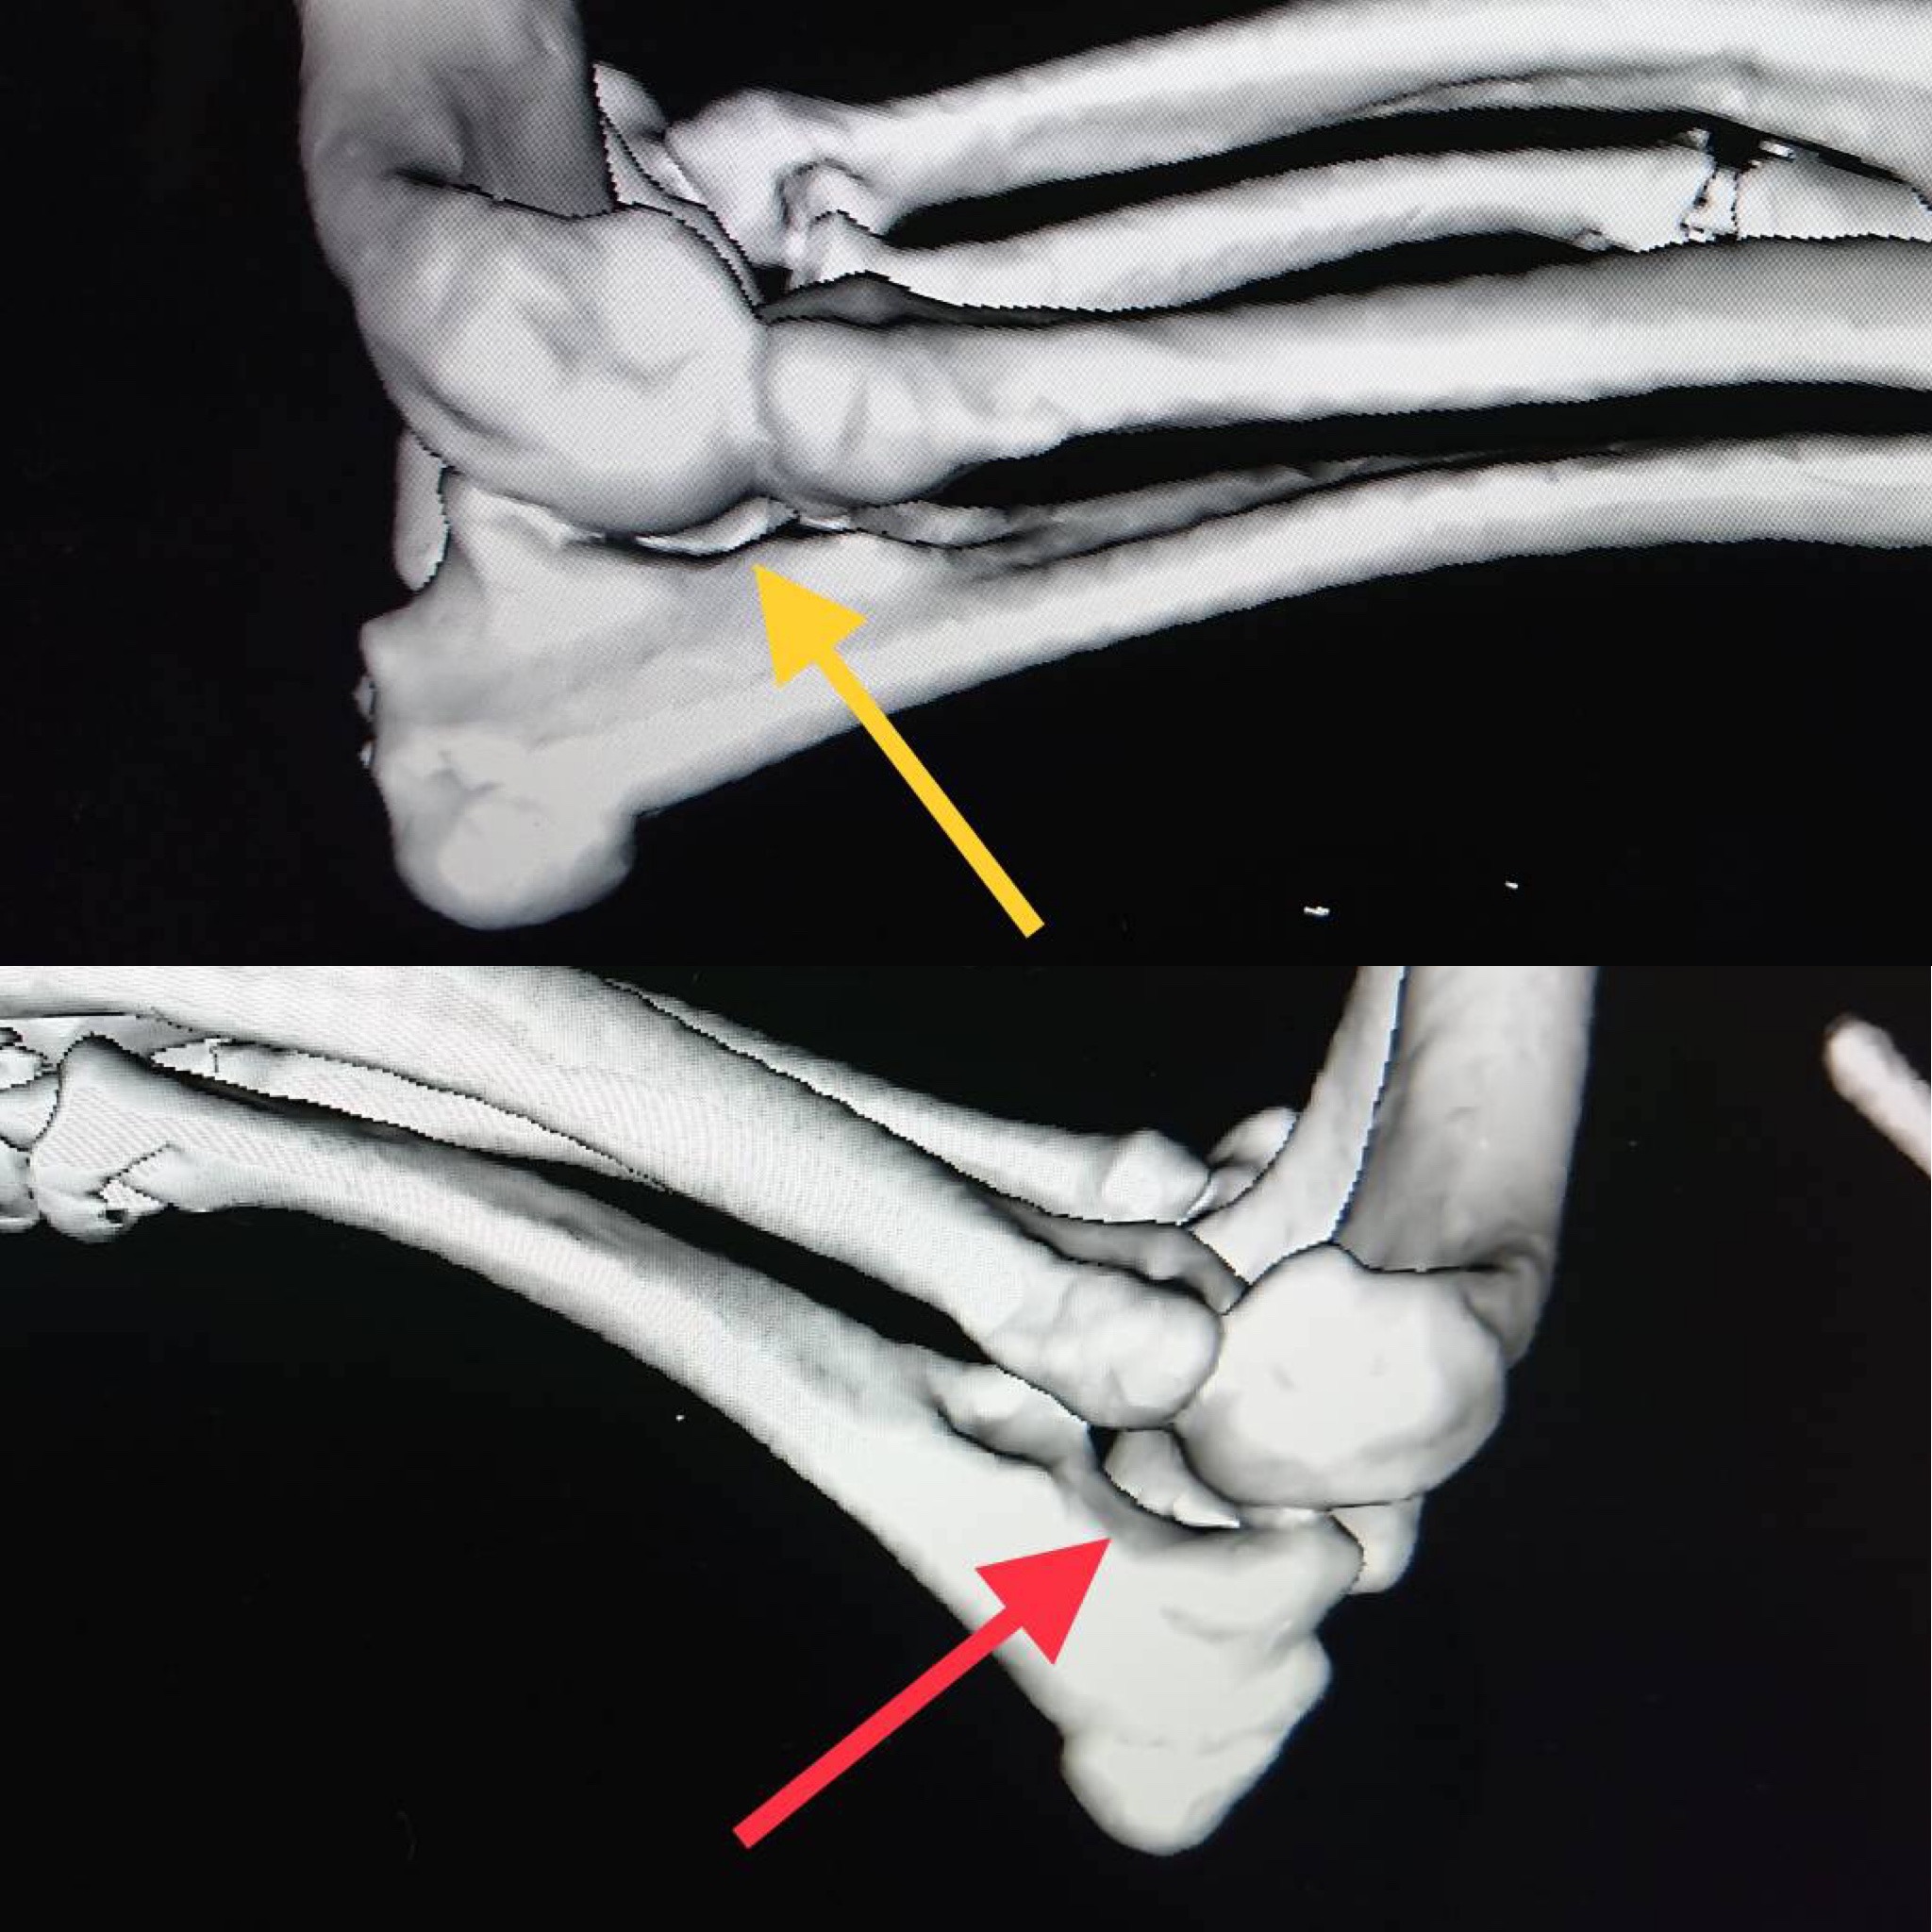

術前計画としてCT検査を実施し、肘関節の整合性を確認した後に、橈骨の湾曲防止と肘関節の不整合を矯正するために尺骨の骨切術を実施しました。

CT画像検査 (黄矢印:左前肢の肘関節 赤矢印:尺骨の遠位成長板早期閉鎖により橈骨のみが伸長し、上腕骨顆が橈骨に押されて間隙を認める右前肢の肘関節)